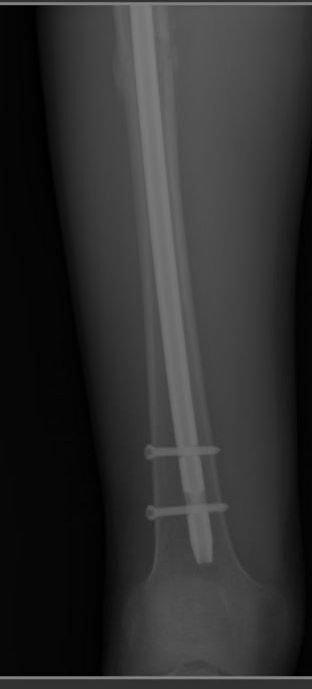

На картинке вы видите стержень внутри бедренной кости. Слева вверху - головка бедренной кости. Толстый винт, который идет через стержень в головку - шеечный винт. Он не дает стержню смещаться. Перелом здесь, если не ошибаюсь, чрезвертельный

Вы видите на картинке линию перелома, которая идет от большого вертела к малому? Для того, чтоб вам было понятнее, приведу картинку строения бедренной кости